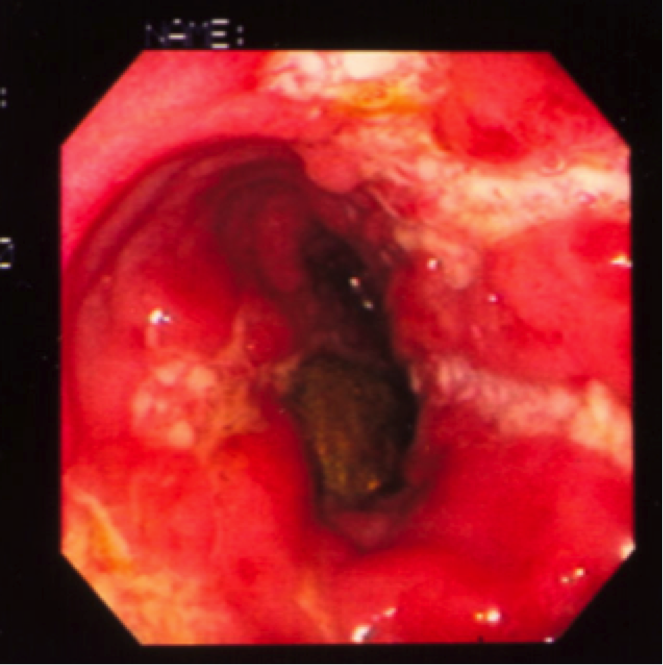

Which disease? features?

Crohn’s.

Aphthous Ulcers.

aphthae are visible grossly as tiny, discrete, punched-out ulcers, often filled with white exudates, and separated by intervening normal-appearing mucosa (circular panel). In a closer-up view (rectangular panel), an erythematous “halo” characteristically surrounds each tiny ulcer.